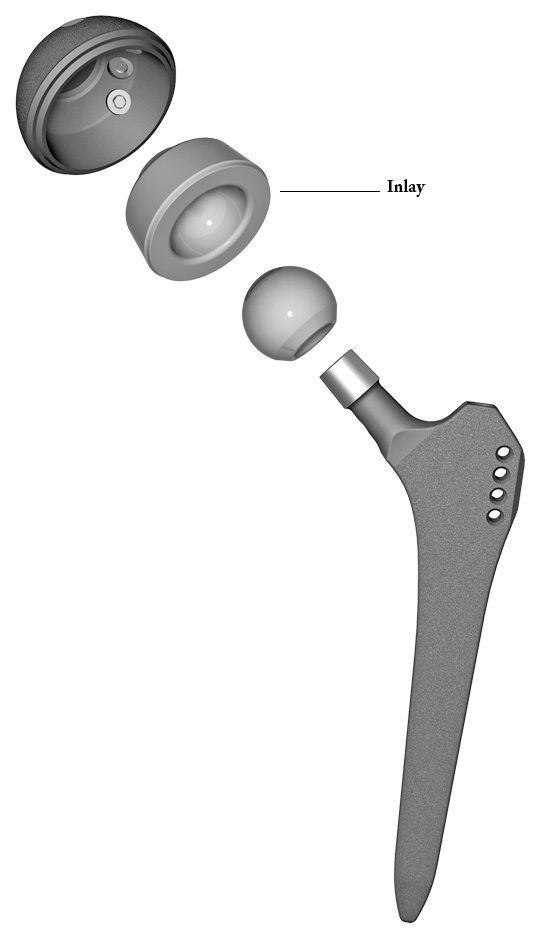

Una protesi articolare è composta da uno stelo femorale di solito in titanio, una coppa acetabolare anch'essa in titanio. La testa femorale e l'inlay sono disponibli in metallo, polietilene oppure ceramica.

A seconda della qualità ossea le componenti possono essere cementate o non.